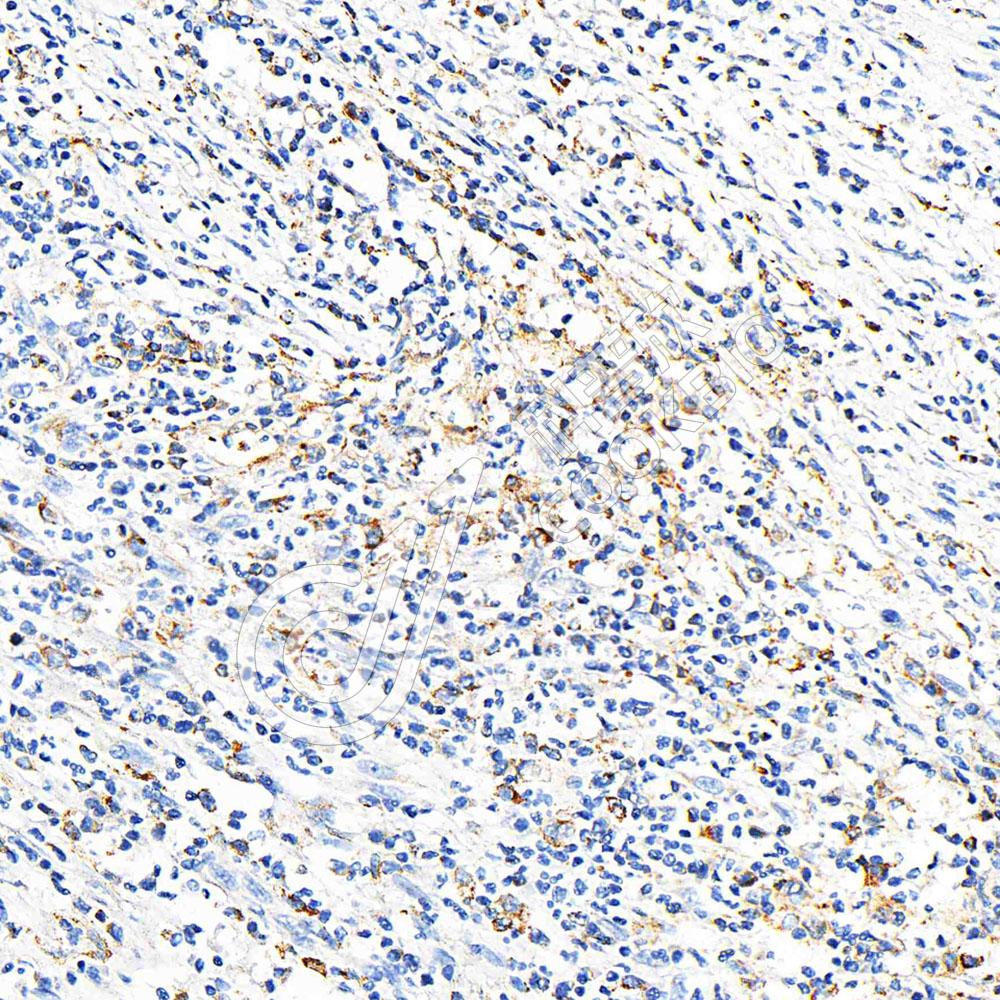

IHC检测CD3蛋白(货号 K1334011).

样品: 小鼠脾, 4%多聚甲醛 (货号KSG1101) 固定12-24小时.

抗原修复: 柠檬酸抗原修复液(干粉, pH 6.0) (KSG1201), 高压锅均匀喷气计时2分钟.

—抗: 1: 1100稀释, 4℃ 孵育过夜.

二抗: S-vision免疫组化多聚二抗(山羊抗兔),即用型 (货号KB3906), 室温孵育20分钟.